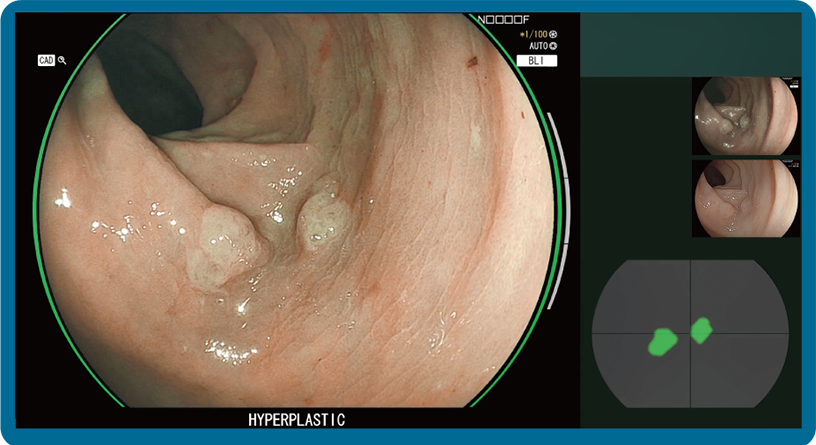

CAD EYE is FUJIFILM's brand name of computer-aided diagnosis (CAD) function for endoscopy. CAD EYE has been developed utilizing AI deep learning technology with an immense amount of clinical images.

Characterization